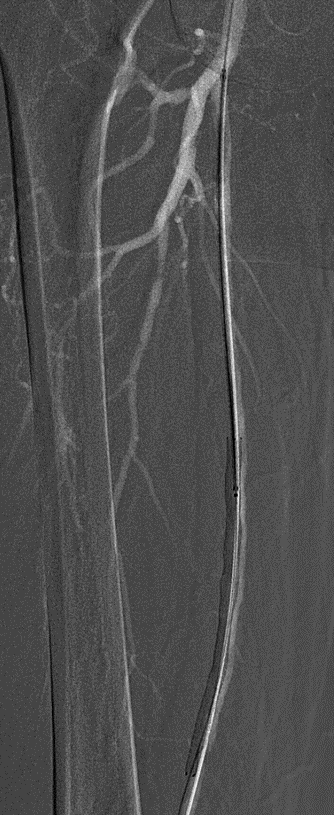

预扩:充分预扩张至关重要,需逐级使用高压球囊,最终达到 6mm 直径,以获得足够的管腔。

支架植入:遵循“由远及近”原则,先放置远端 DES,再覆盖中段 VB,最后处理近端。利用 Eluvia 的可调节性优化重叠。

后扩:常规使用 6mm 高压球囊进行后扩张,确保支架充分贴壁和管腔获得。